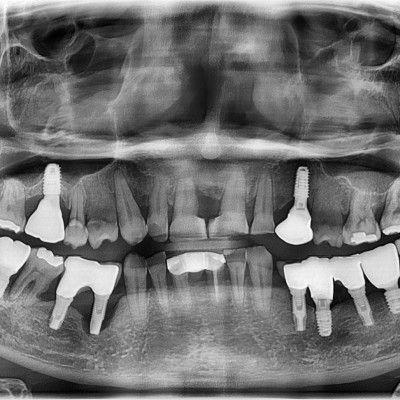

임플란트 재수술

임플란트 재수술♥ 타원 #31.32.41.42.44.45.46.47 제거 후 #33.34.35.43.44.45로 all on x 진행하였습니..